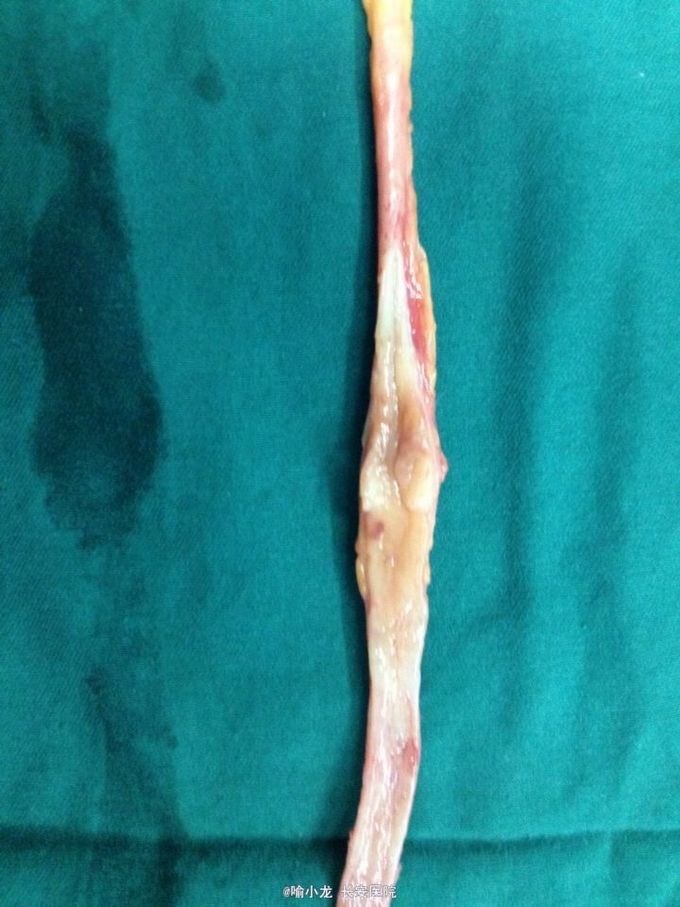

入院查血常规、肝肾功能、电解质、血脂六项、凝血四项、肿瘤四项、粪常规均基本正常;尿液分析示潜血3+,白细胞+;入院留48小时尿培养阴性;血型鉴定B型,血气分析、输血前四项基本正常;心电图、心脏彩超、腹部彩超、胸片及胸部CT检查均大致正常;下腹部+盆腔CT示左侧肾盂伴左侧输尿管全程扩张,右侧肾囊肿大小约2.0cmx1.3cm;泌尿系水成像示右肾囊肿约1.4cm,左侧输尿管上段内见条形低信号影。初步诊断:1.左侧输尿管肿瘤;2.左侧肾盂积水;3.右侧肾囊肿;4.泌尿系感染;5.高血压3级。入院后抗感染、止血对症治疗后,阵发性血尿无缓解,出现左侧肾绞痛伴发热乏力,遂急诊行膀胱镜检查并置入输尿管导管,术后阵法性血尿仍不缓解,2天后在静脉全麻下急诊行膀胱输尿管镜检查+左侧双J管置入术,术后间断寒战发热,最高体温39℃,化验尿培养示大肠埃希氏菌,病检示左输尿管高级别乳头状尿路上皮癌,根据药敏抗感染疗5天后,体温渐恢复并稳定,4天后在全麻下行左侧肾脏输尿管根治性切除术,术后病理示输尿管中段高级别乳头状尿路上皮癌局灶侵及固有层,外膜未见癌侵润,术后恢复良好。